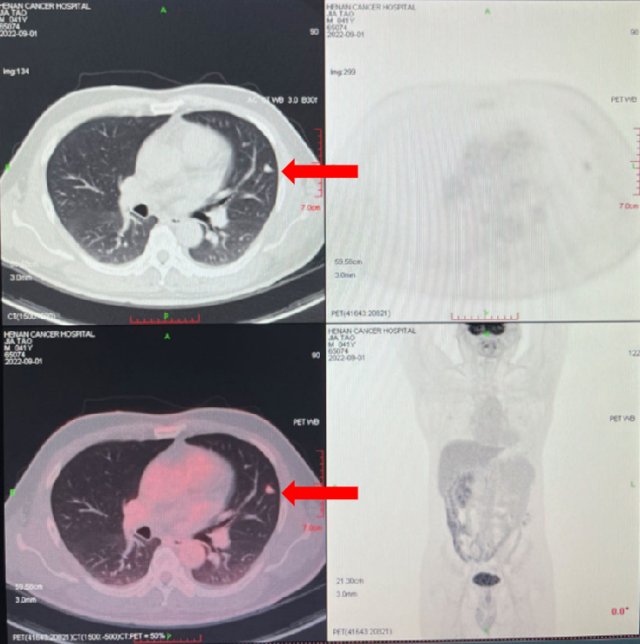

影像学检查

2023-08-01: